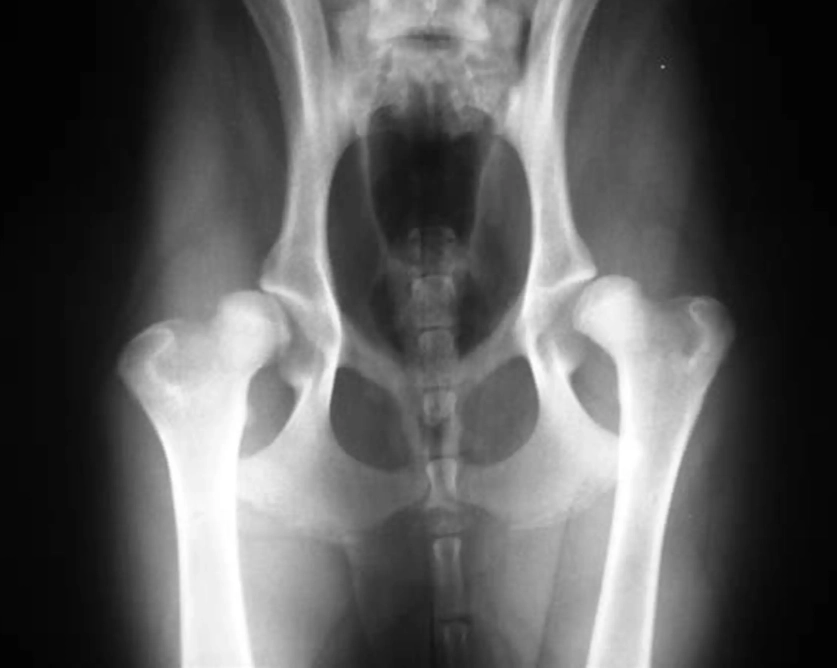

Let's break it down simply. A healthy hip is a ball-and-socket joint that fits together snugly. With hip dysplasia, the socket is too shallow, and the ball (the head of the femur) is loose. This poor fit causes abnormal wear and tear every time the dog moves. It's not just arthritis—arthritis is the result of the instability. The condition is primarily genetic, but factors like rapid growth, improper nutrition, and excessive exercise in puppyhood can worsen it.

- X-Rays (Radiographs): This is the gold standard. But not all X-rays are equal. A quick, awake X-ray often misses the true degree of laxity. For a definitive diagnosis, especially in young dogs, a hip-extended ventrodorsal view and often a PennHIP or Dorsal Acetabular Rim (DAR) view are needed. PennHIP, in particular, can detect laxity in puppies as young as 16 weeks, which is a game-changer for early intervention.